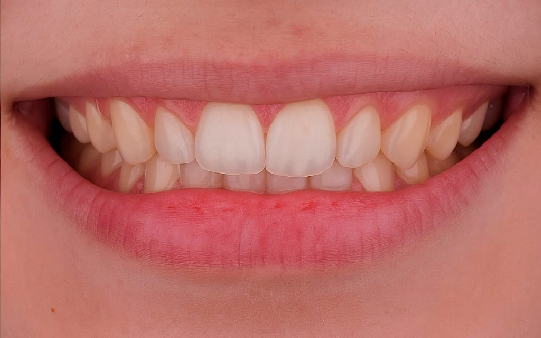

Baixa autoestima e dificuldade para sorrir